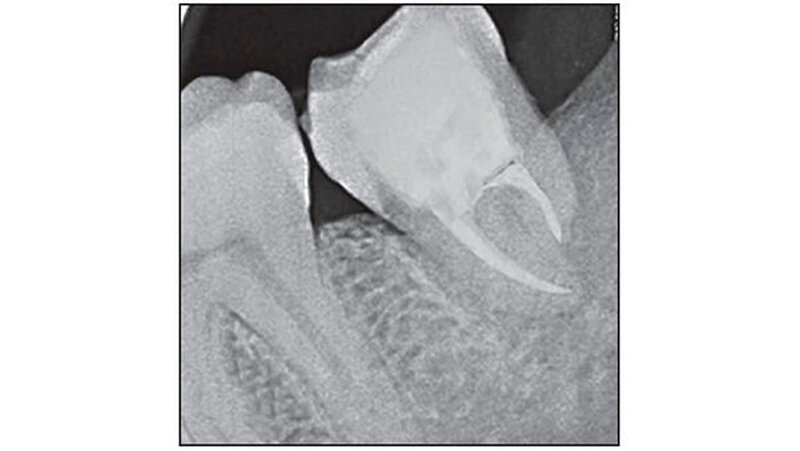

Eine 27-jährige Patientin stellte sich mit Schmerzen im linken Unterkiefer in der Abteilung für Zahnerhaltung und Endodontie am Himachal Dental College in Himachal Pradesh , Indien, vor. Die klinische und radiologische Untersuchung ergab, dass der Zahn 37 stark kariös war. Zudem lag eine chronische irreversible Pulpitis und apikale Parodontitis vor. Der Zahn 38 zeigte horizontale Einbrüche (Abbildung 1). Daher wurde beschlossen, 37 und 38 gleichzeitig zu extrahieren und den 38 in die Extraktionsstelle des 37 zu transplantieren.

Die Anästhesie erfolgte mit Lidocain-Hydrochlorid (Lignox zwei Prozent, Indoco-Remedies Ltd., India). Zuerst erfolgte die Extraktion von Zahn 37 extrahiert - ohne die Corticales zu beschädigen. Danach erst erfolgte die Extraktion von Zahn 38, um hier die Gewebeschäden so gering wie möglich zu halten. Eine horizontale intrakrevikuläre Inzision wurde durchgeführt. Zahn 38 wurde bis zur Transplantation in isotoner Kochsalzlösung gelagert, parallel eine Socket Preparation vorbereitet (Abbildung 2).